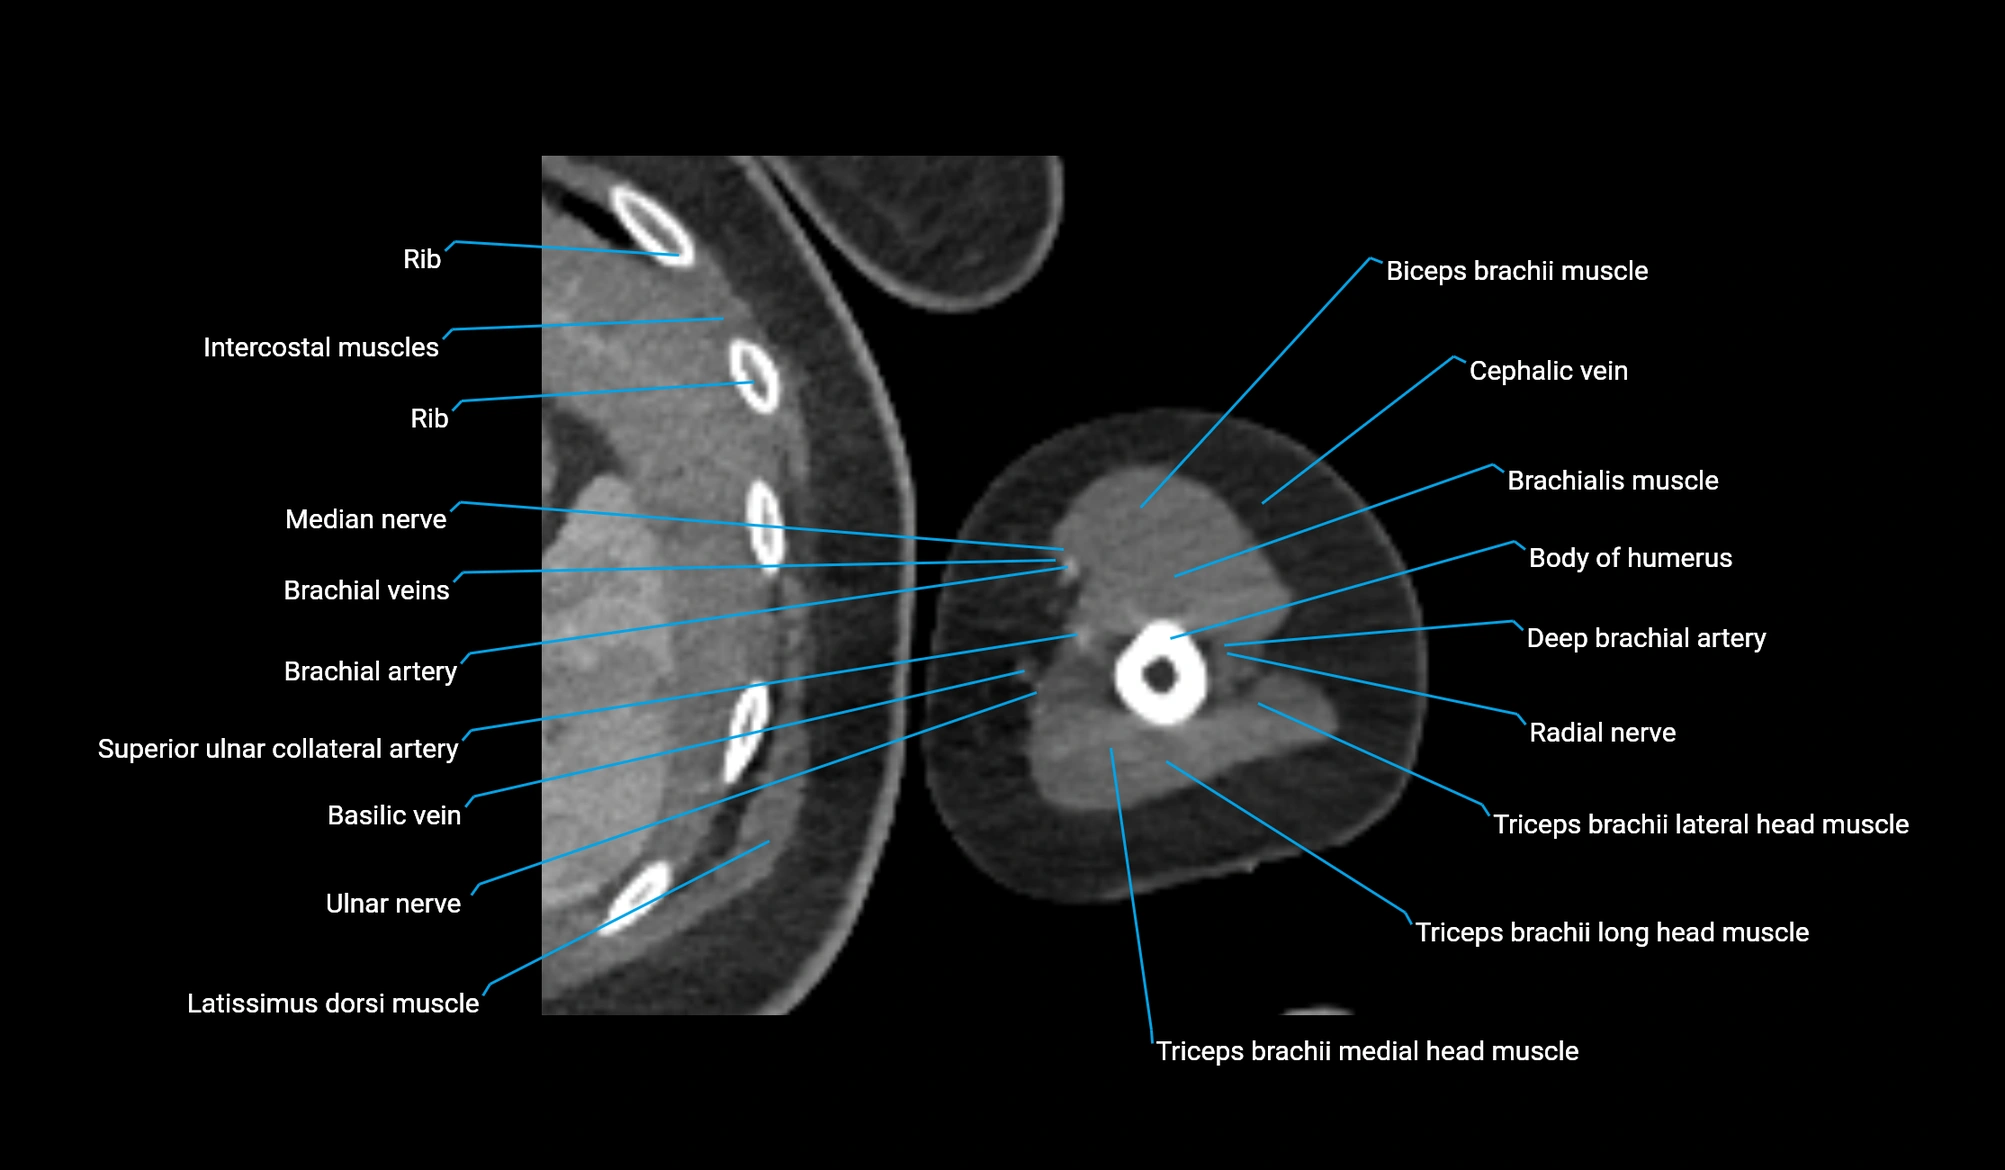

CT Appearance

Non-Contrast CT:

-

Muscle: soft-tissue density, well defined in the hypothenar region.

Tendon: linear low-density structure extending to the base of the little finger.

Calcification or chronic scarring may appear as localized high-density foci.

Useful for assessing bony attachment sites at the pisiform and proximal phalanx.